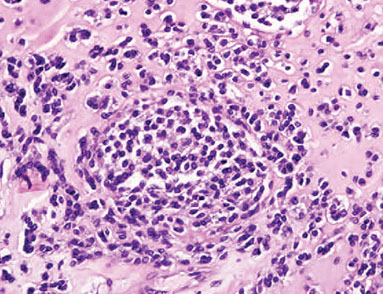

Hypersensitivity pneumonitis. The main abnormality is mild thickening of the alveolar septa (interstitium). Granulomas are not visible at this mag.

Hypersensitivity pneumonitis. Interstitial chronic inflam c a loose cluster of histiocytes (poorly formed granulomas)